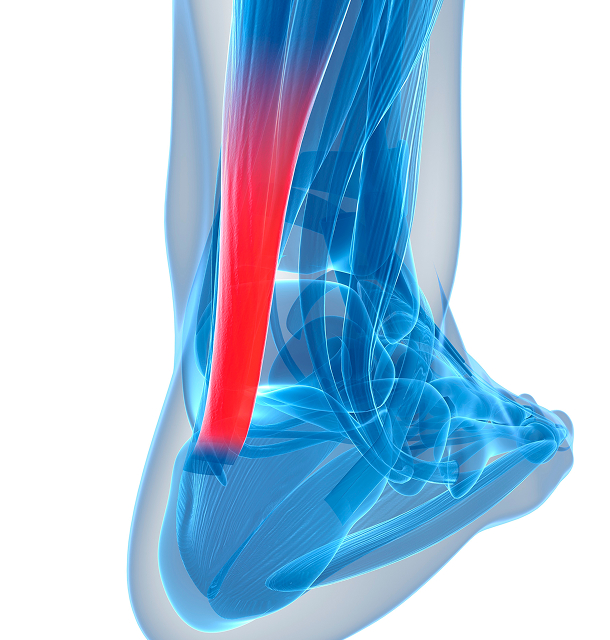

아킬레스 건염

발뒤꿈치와 종아리를 연결하는 아킬레스 건의 염증

Achilles Tendinitis

아킬레스 건염이란?

아킬레스건은 발뒤꿈치 뼈에서 무릎까지 연결되는 힘줄로 발목의 과도한 사용으로 아킬레스건에 염증이 생기는 질환을 아킬레스건염이라고 합니다.

장딴지 근육의 지나친 경직, 크거나 꽉 끼는 신발 착용, 달리기 등 운동을 무리하게 할 경우 염증이 발생하기 쉽습니다.

아킬레스 건염의 원인

- 1잘못된 준비운동

- 2격렬한 스포츠활동

- 3외부로부터의 충격으로 인한 손상

아킬레스 건염 증상

아킬레스건에서 열이 나며

붓는 증상이 있음 -

종아리에 통증이 있음 /

발목에서 소리가 남 -

아침에 첫걸음을 내딛을 때

통증이 있음 -

발바닥에 통증이 있음